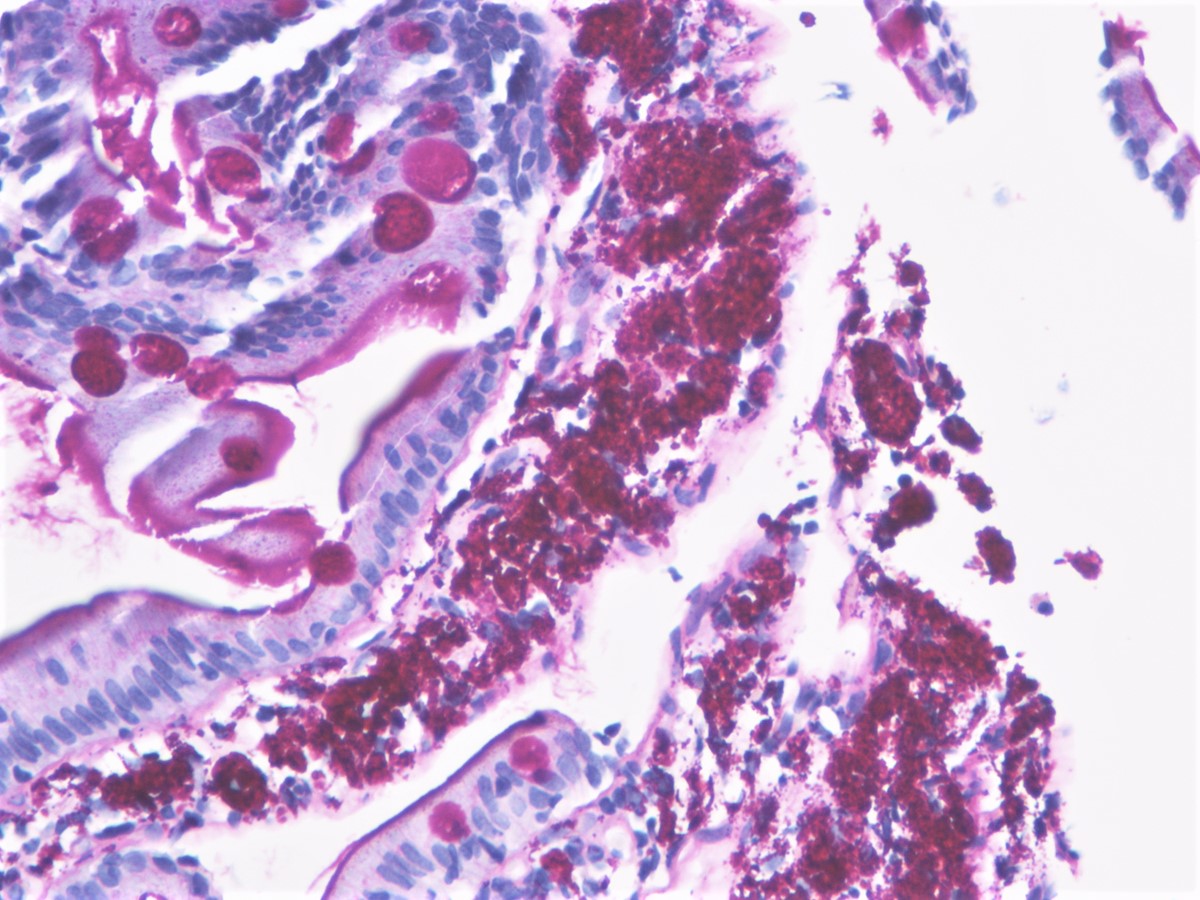

Фотографии медицинских исследований инсулиномы и синдрома Триады Уиппла